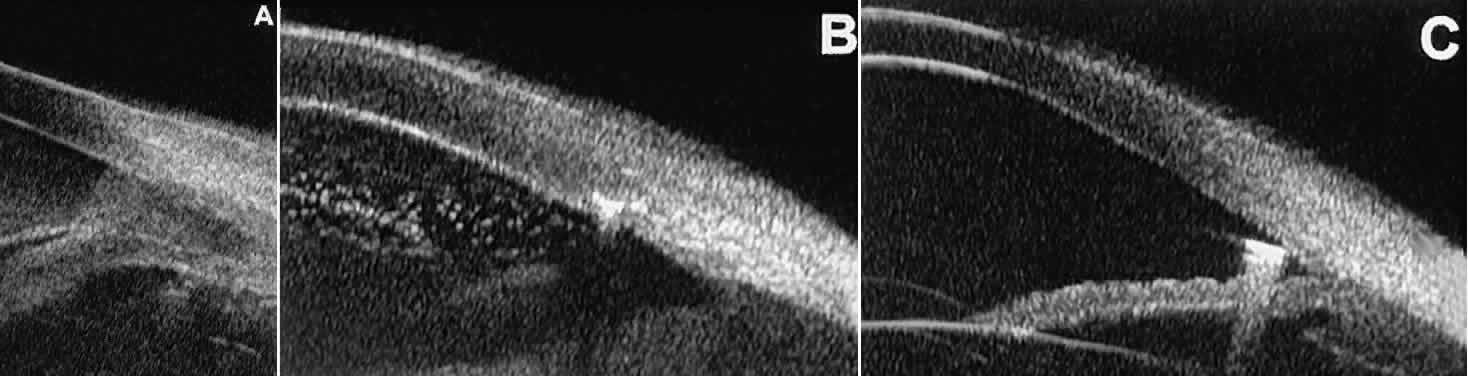

In open-angle glaucoma, UBM can be used to measure the anterior chamber angle in degrees, to assess the configuration of the peripheral iris, and to evaluate the trabecular meshwork (Fig. 9).2,4 The angle configuration can be graded and compared with gonioscopic findings. In certain patients with open-angle glaucoma, UBM can provide information that may be of some diagnostic value (Fig. 10). For example, in pigment dispersion syndrome (see Fig. 10A),6 UBM typically reveals posterior bowing of the peripheral iris (“q” configuration of peripheral iris by Spaeth classification5). In plateau iris syndrome (see Fig. 10B),7 UBM usually reveals abnormally steep anterior angulation of the peripheral iris (“s”configuration of peripheral iris by Spaeth classification5), insertion of the iris from the anterior ciliary body, and retroiridic projection of the ciliary processes. In eyes with peripheral anterior synechiae (see Fig. 10C and D), UBM can reveal the extent of iridocorneal adhesion even if the cornea is hazy or opaque.

Fig. 10. UBM features of special glaucoma cases. A. Pigment dispersion syndrome with posterior bowing of peripheral iris (“q” configuration by Spaeth gonioscopic grading system). B. Plateau iris syndrome with origin of iris from anterior surface of ciliary processes behind peripheral iris, slitlike narrowing of peripheral angle, and abrupt transition from steep peripheral iris to flat iris midzone. C. Broad peripheral anterior synechia with posterior bowing of nonadherent iris. D. Peripheral anterior synechia with aqueous-filled slit between site of iridocorneal adhesion and iris root after cataract extraction with implantation of posterior-chamber IOL.

In eyes with a narrow angle, UBM shows the extent of angle closure, reveals the depth of the anterior and posterior chambers, and identifies pathologic processes pushing the lens and iris forward (Fig. 11).2–4,8 UBM has been able to differentiate between primary angle closure (i.e., cases of angle closure without additional pathology responsible for the anterior lens-iris displacement [see Fig. 11A] and secondary angle closure due to processes such as lens swelling and dislocation (see Fig. 11B), massive hemorrhagic retinal detachment pushing the lens and iris anteriorly (see Fig. 11C), and multiple neuroepithelial cysts of the iridociliary sulcus (see Fig. 11D).

Fig. 11. Angle configuration in eyes with angle-closure glaucoma. A. Primary angle-closure glaucoma with anterior displacement of lens and iris. B. Angle closure secondary to swollen, cataractous lens (phakomorphic angle closure). C. Angle closure secondary to massive hemorrhagic retinal detachment; the subretinal blood is evident in the lower right corner of the photograph. D. Angle closure secondary to multiple peripheral iris cysts.